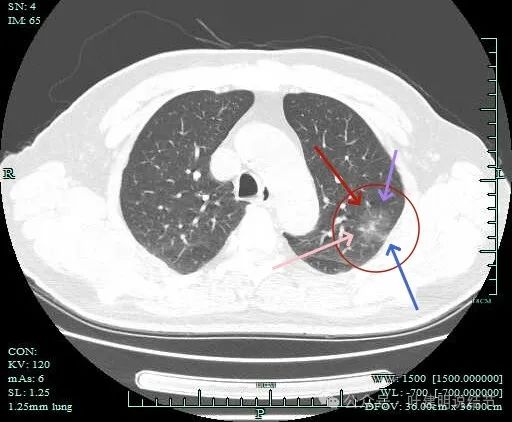

病灶肺表面近,整体轮廓与边界清,表面不平,灶内有小空泡征。

灶内密度感觉欠均匀,虽然无明显实性成分。

灶内似有血管穿行与小空泡征,表面有细毛刺。